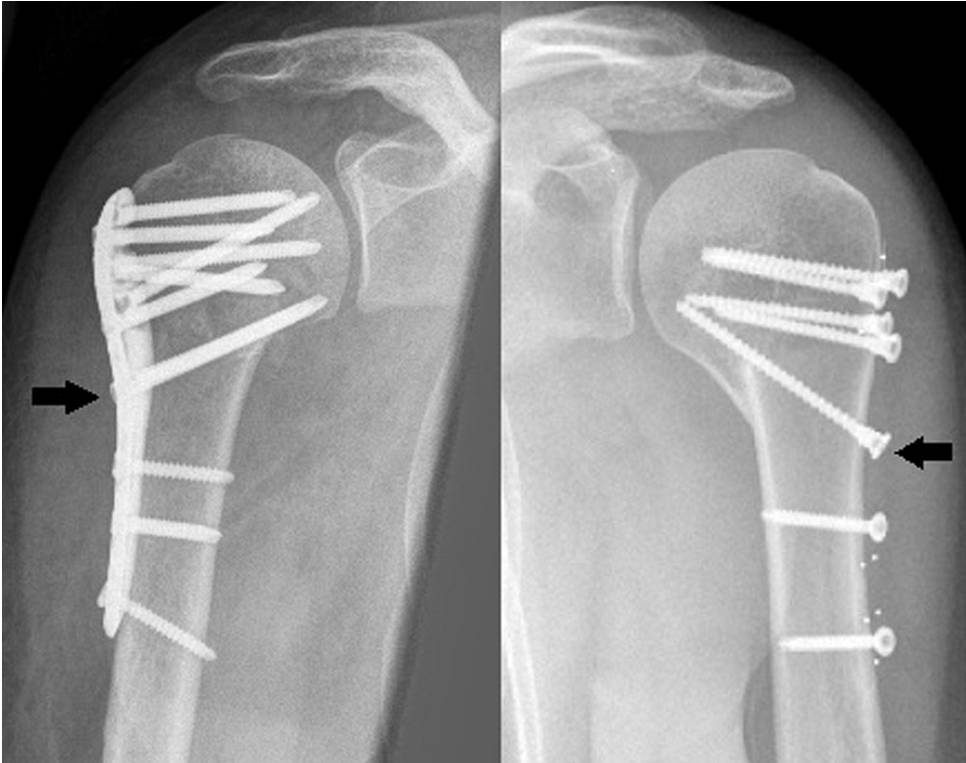

骨水泥加强固定已经成功运用于肱骨近端骨折的处理上。磷酸钙和硫酸钙骨水泥均可用在肱骨近端骨折时填充于骨折间隙,尤其是干骺端骨折间隙的处理上。头螺钉采用骨水泥强化固定可在打钉前先打入骨水泥或者使用空心钉皆可,这两类方法都已在临床上取得良好效果(图2)。

图2.

空心钉加用骨水泥强化固定(A),术后影像(B)。